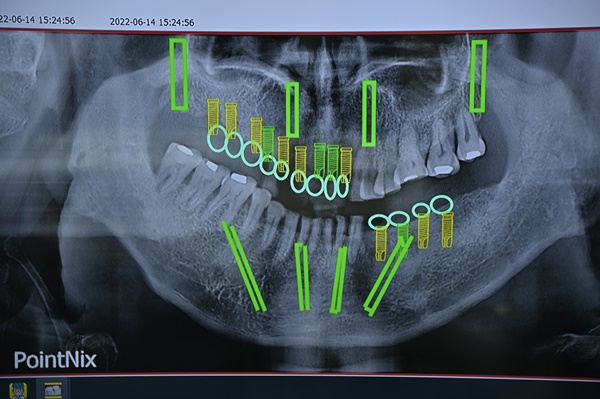

負責幫媽媽規劃療程的是朱裕華醫師,他不只是植牙專科醫師,更是有三十年以上經驗、在中國醫藥大學任教的教授。聽他解說的過程中我真的能感受到他的細心與專業。他先幫媽媽做了詳細的口腔 3D 掃描、骨質檢測,還耐心說明不同植體品牌的差異,連每顆植體要多深、角度怎麼擺都事先規劃好。